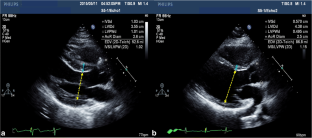

Fig. 1